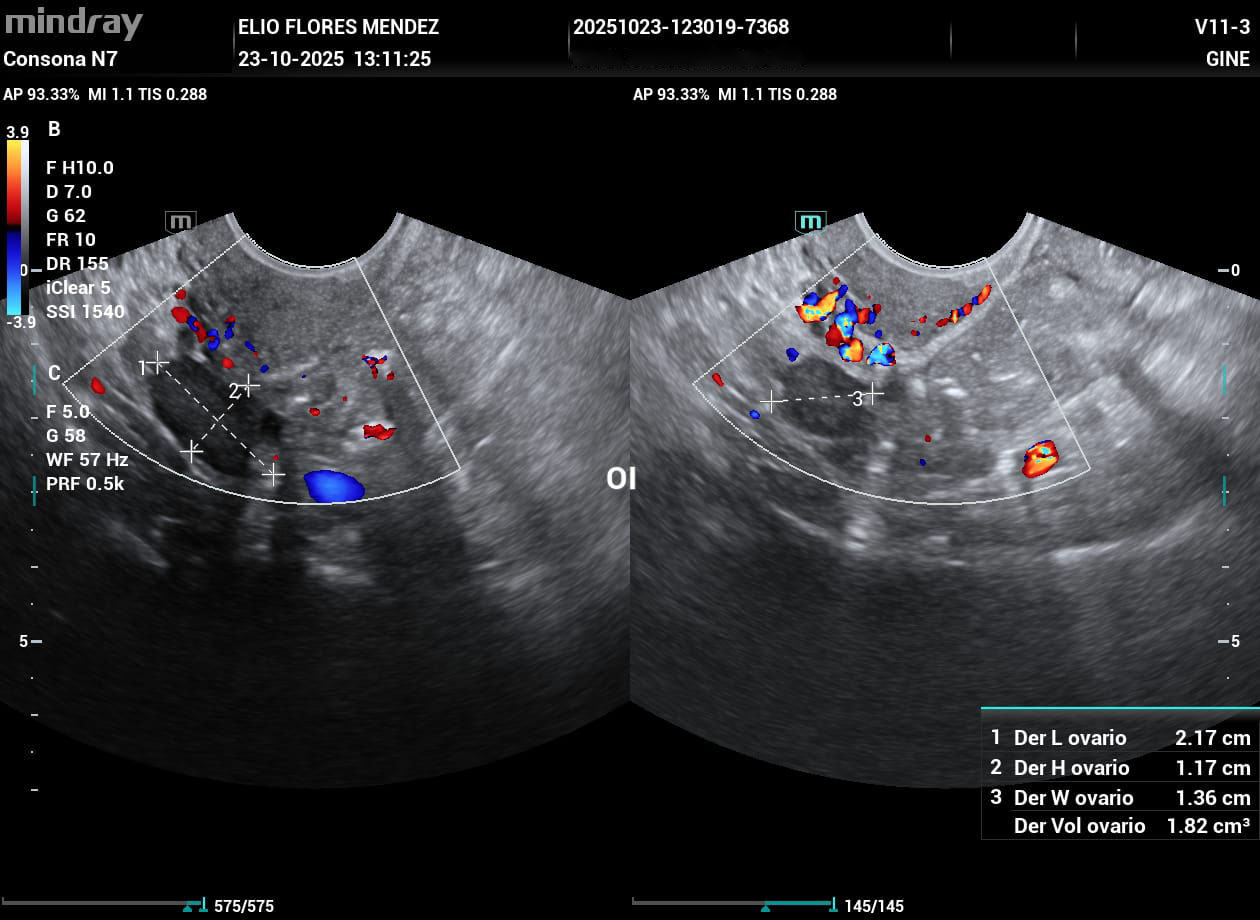

Dr. Elio Flores Méndez

Médico Radiólogo Especialista en Imagenología Diagnóstica y TerapeúticaDr. Francisco Antonio Soto Patiño